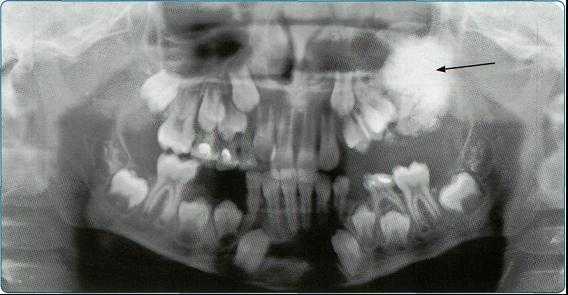

При выявлении на обзорных снимках инородного тела определяют его ориентировочную локализацию, пользуясь широко известным рентген-анато- мическим методом В. С. Майковой-Строгановой.

В случаях, когда предположительная локализация указывает на внутриглазную (или пограничную) локализацию инородного тела, приступают ко второму этапу — локализационной рентгенографии. Для этого (при отсутствии противопоказаний) после эпибульбарной анестезии на глазное яблоко накладывают подходящий по размеру протез Комберга—Балтина, его свинцовые метки ориентируют соответственно циферблату часов и делают три прицельных (без отсеивающей решетки) снимка орбиты с обязательной стандартной фиксацией взгляда.

Рентгенограмма в прямой плоскости. Центрация луча производится «на зрачок», т. е. линии светового центратора, при условном продолжении их с темени на орбиту, должны пересекаться на зрачке, а центральный луч — совпадать с осью глаза. На снимке видна слабая кольцевидная тень протеза и четыре точечные метки. Показателем качества снимка служит почти концентричное положение тени протеза в контуре глазницы. Допускается смещение меток вокруг оси без отклонения глаза (рис. 77, а).

Боковой снимок выполняется в положении лежа на спине боковым лучом с центрацией на наружный угол глаза. На снимке видна трапециевидная тень протеза. Критерий качества снимка — расположение меток протеза на одной линии (см. гл. 13, рис. 125, а). Максимально допустимое расхождение меток на

3- 9 часов — 2 мм (рис. 77, б).

Аксиальный снимок (подбородочная укладка). Взгляд фиксируется прямо вперед параллельно столу. На снимке видна тень протеза со свинцовыми метками (см. гл. 13, рис. 125, б). Об удовлетворительном качестве снимка свидетельствует расположение меток на одной линии. Максимально допустимое расхождение меток, обозначающих 6 и 12 часов, — 2 мм.